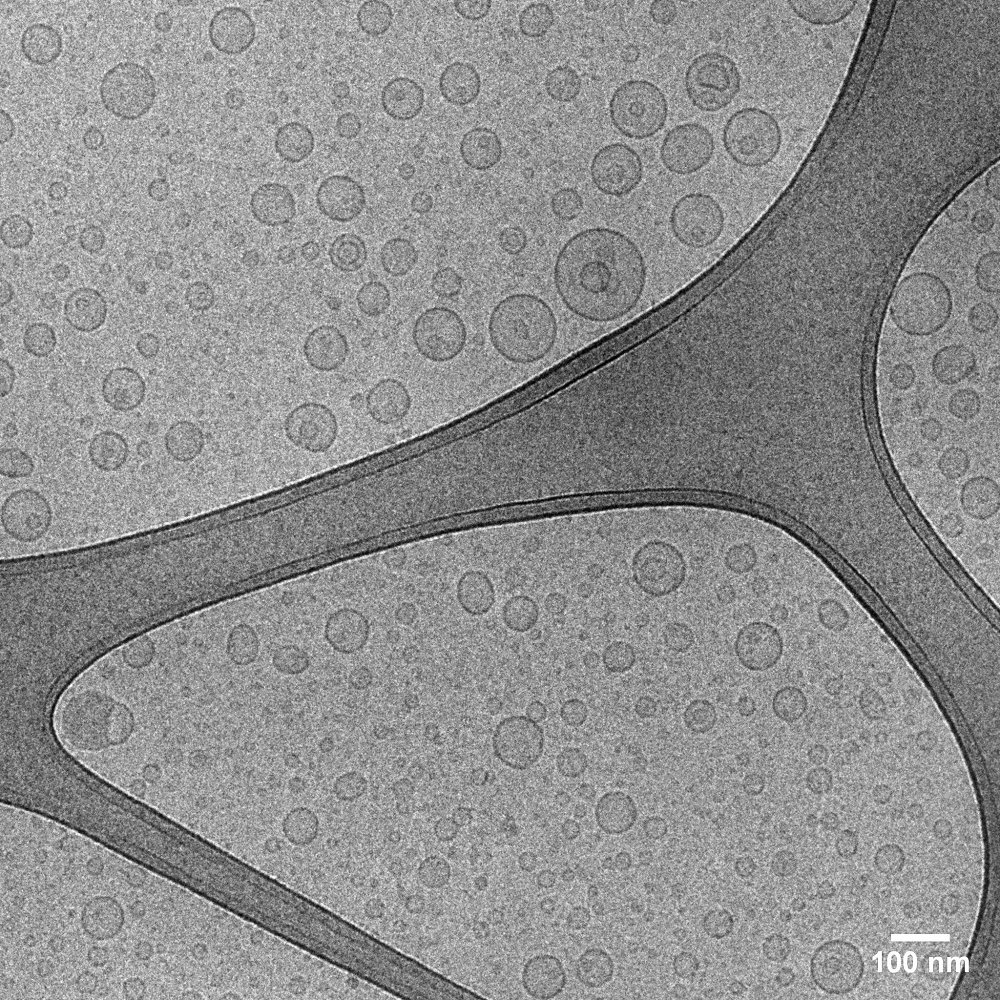

Imagem de criomicroscopia de lipossomas pH-sensíveis compostos por succinato de tocoferila e doxorrubicina, desenvolvidos para tratamento de tumor de mama experimental.

Equipamento: Microscópio Eletrônico de Transmissão Tecnai G2-12 – Spirit Biotwin FEI 120kV

Imagem cedida por Elaine Amaral Leite e Fernanda Alves Boratto, Departamento de Produtos Farmacêuticos, Faculdade de Farmácia, UFMG